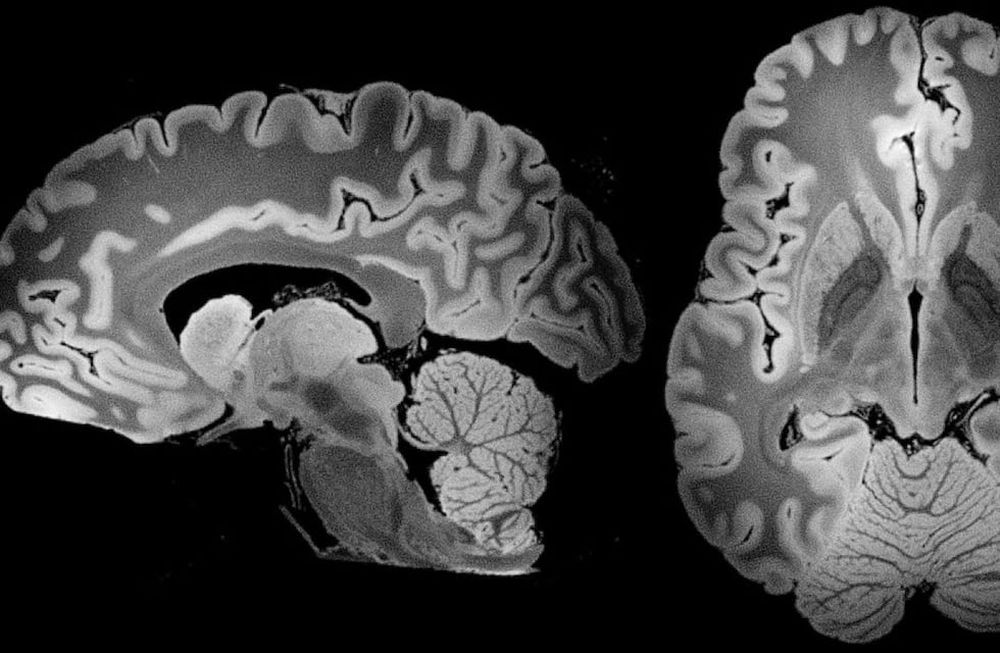

En mayo de 2024, investigadores de la Universidad de Nuevo México encontraron un aumento en las concentraciones de microplásticos y nanoplásticos en el cerebro humano. En comparación con muestras de 2016, las de 2024 contenían un 50% más de partículas, sumando aproximadamente 4,800 microgramos de microplásticos por gramo de tejido cerebral. Este estudio, que todavía está pendiente de revisión entre otras instituciones, reveló que los microplásticos representan el 0.5% del cerebro humano.

El análisis involucró muestras de cerebro, hígado y riñones de 92 personas sometidas a autopsias. Se observó que el cerebro atrae partículas más pequeñas, mientras que las más grandes se acumulan en el hígado y los riñones.

Los microplásticos, de menos de 5 milímetros, y los nanoplásticos, de menos de 80,000 nanómetros, pueden atravesar la barrera hematoencefálica y alterar funciones neurológicas.